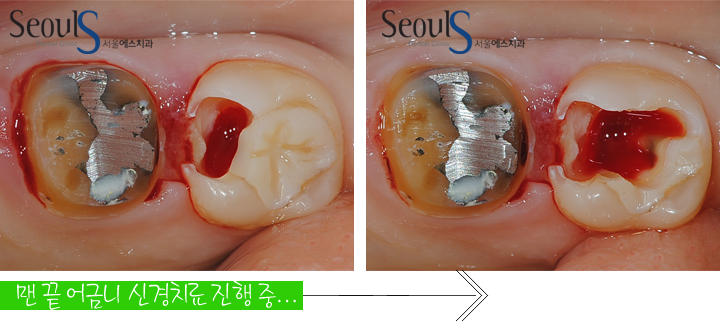

통증이 있던 맨 끝 어금니는 충치가 신경까지 진행된 상태로

신경치료를 진행하고 있습니다

신경 노출로 치아 속에서 탁한 피가 나고 있습니다

만약 충치를 제거하다

맑은 피가 나오거나 염증 초기라면

MTA 신경보호 치료로 신경치료를 피할수 있습니다